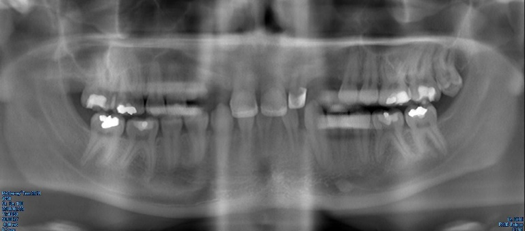

Fig 5. Panoramic radiograph, 18-year-old brother.

Figure 5

Figure 5 through Figure 12 exemplify what currently may present in private dental practices with these types of patients. Four brothers aged 14 years to 27 years all suffered from obstructed airways; high incidence of caries of dentin, enamel, and cementum; moderate periodontal disease; collapsed vertical; undiagnosed OSA; and the potential for increase in comorbidities such as diabetes, cardiovascular disease, dementia, cancer, high blood pressure, and others. Symptomology was presented throughout the young lives of the brothers in this family. The parents were unaware that the dental agenesis and premature permanent tooth extraction could have led their sons into severe health issues as they matured.

Familial Case of Dental Agenesis

Four brothers with dental agenesis are currently being evaluated and treated by the author with CBCT imaging and digital treatment planning to regain their dentition. Developing arch form and palatal positioning by using CBCT imaging and digital software is critical. Much is learned from evaluating CBCT images and the advancement of virtual implant therapies. Combined with durable medical equipment and orthopedic/mandibular repositioning appliances, normal daytime breathing and normal sleep breathing patterns can be achieved through surgical dental implant services, orthodontic services, and long-term dental restorations that reposition the mandible and create a comfortable tongue position within the oral cavity. In the author's experience, CBCT in these situations provides a considerable amount of diagnostic information, improves quality of life, and improves the opportunity to enjoy a healthier lifestyle without the previously mentioned diseases of civilization.